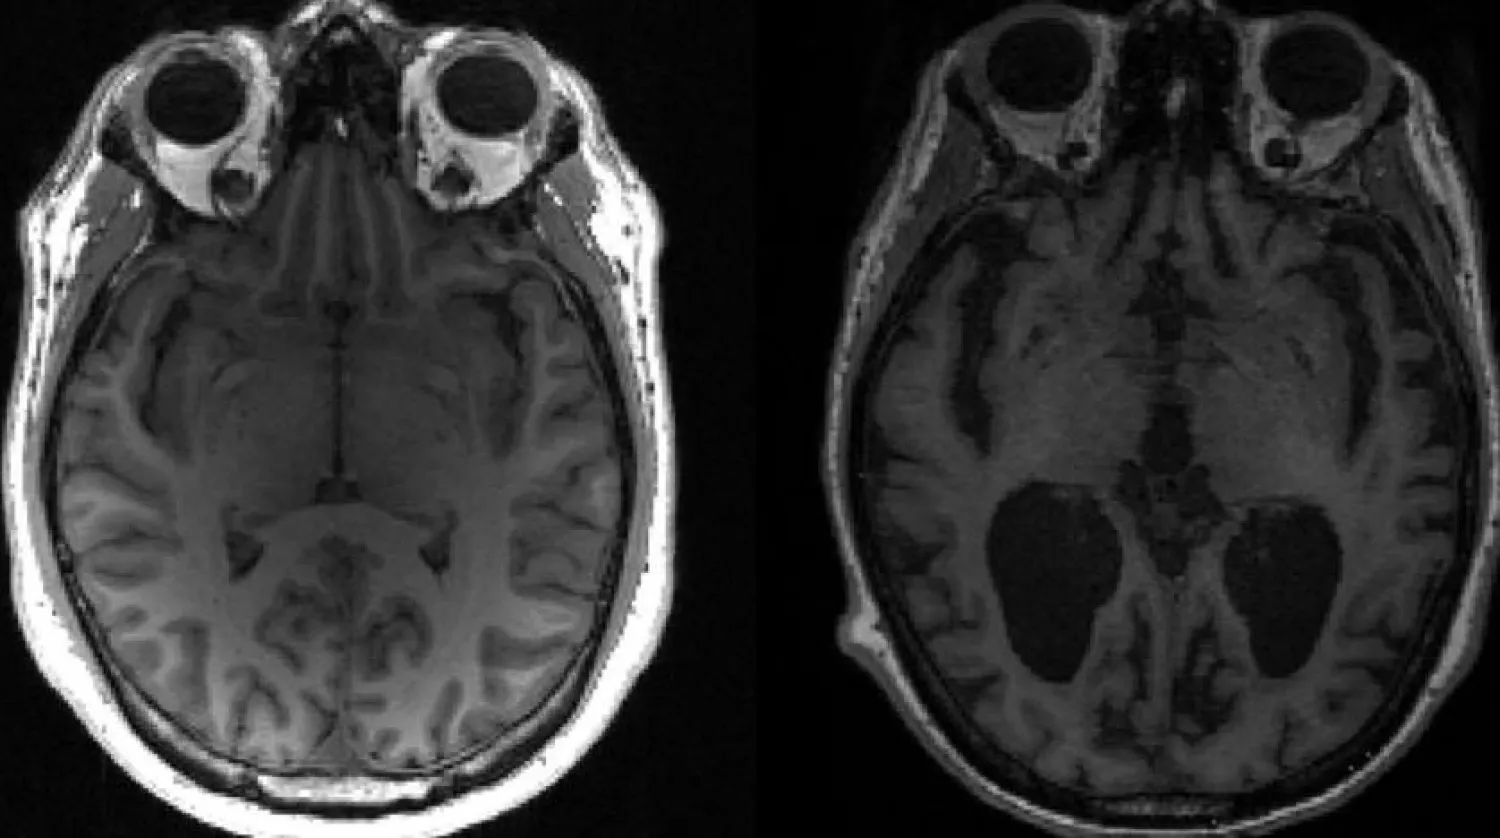

This undated image courtesy of, Dr. Timothy Rittman, University of Cambridge, shows an MRI image of a healthy brain (L) and an Alzheimer's brain (R) with large black gaps where brain has shrunk. (AFP)

In Alzheimer's disease, two key proteins, tau and amyloid beta, build up into tangles and plaques, known together as aggregates, which cause brain cells to die and lead to brain shrinkage.